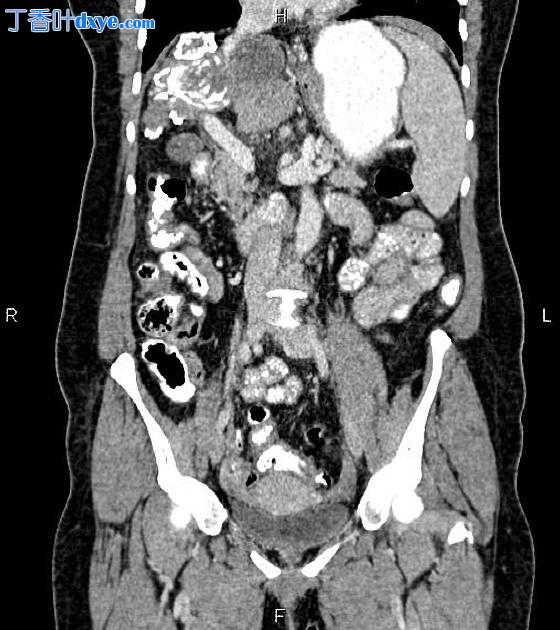

Coronal C+ portal venous phase

部分右肝叶切除术后的变化。

残余的右肝叶有一个 70 × 50 mm 的钙化病变。 在左肝叶中还发现了一个 22 × 20 毫米的较小的。 此外,尾状叶有一个 44 × 41 mm 的囊性病灶,边缘有小的钙化灶。

腹壁右前外侧有一个 22 毫米的筋膜缺损,一些网膜脂肪通过它突出。

在下胸腔的成像部分; 在右下叶发现一个 18 毫米的结节性病变 (37 HU)。 此外,在右心膈角观察到一个 35 × 20 mm 的囊性病变。

钙化和部分钙化的肝包虫囊肿。

右心膈角囊肿; 包虫与心包囊肿不同。